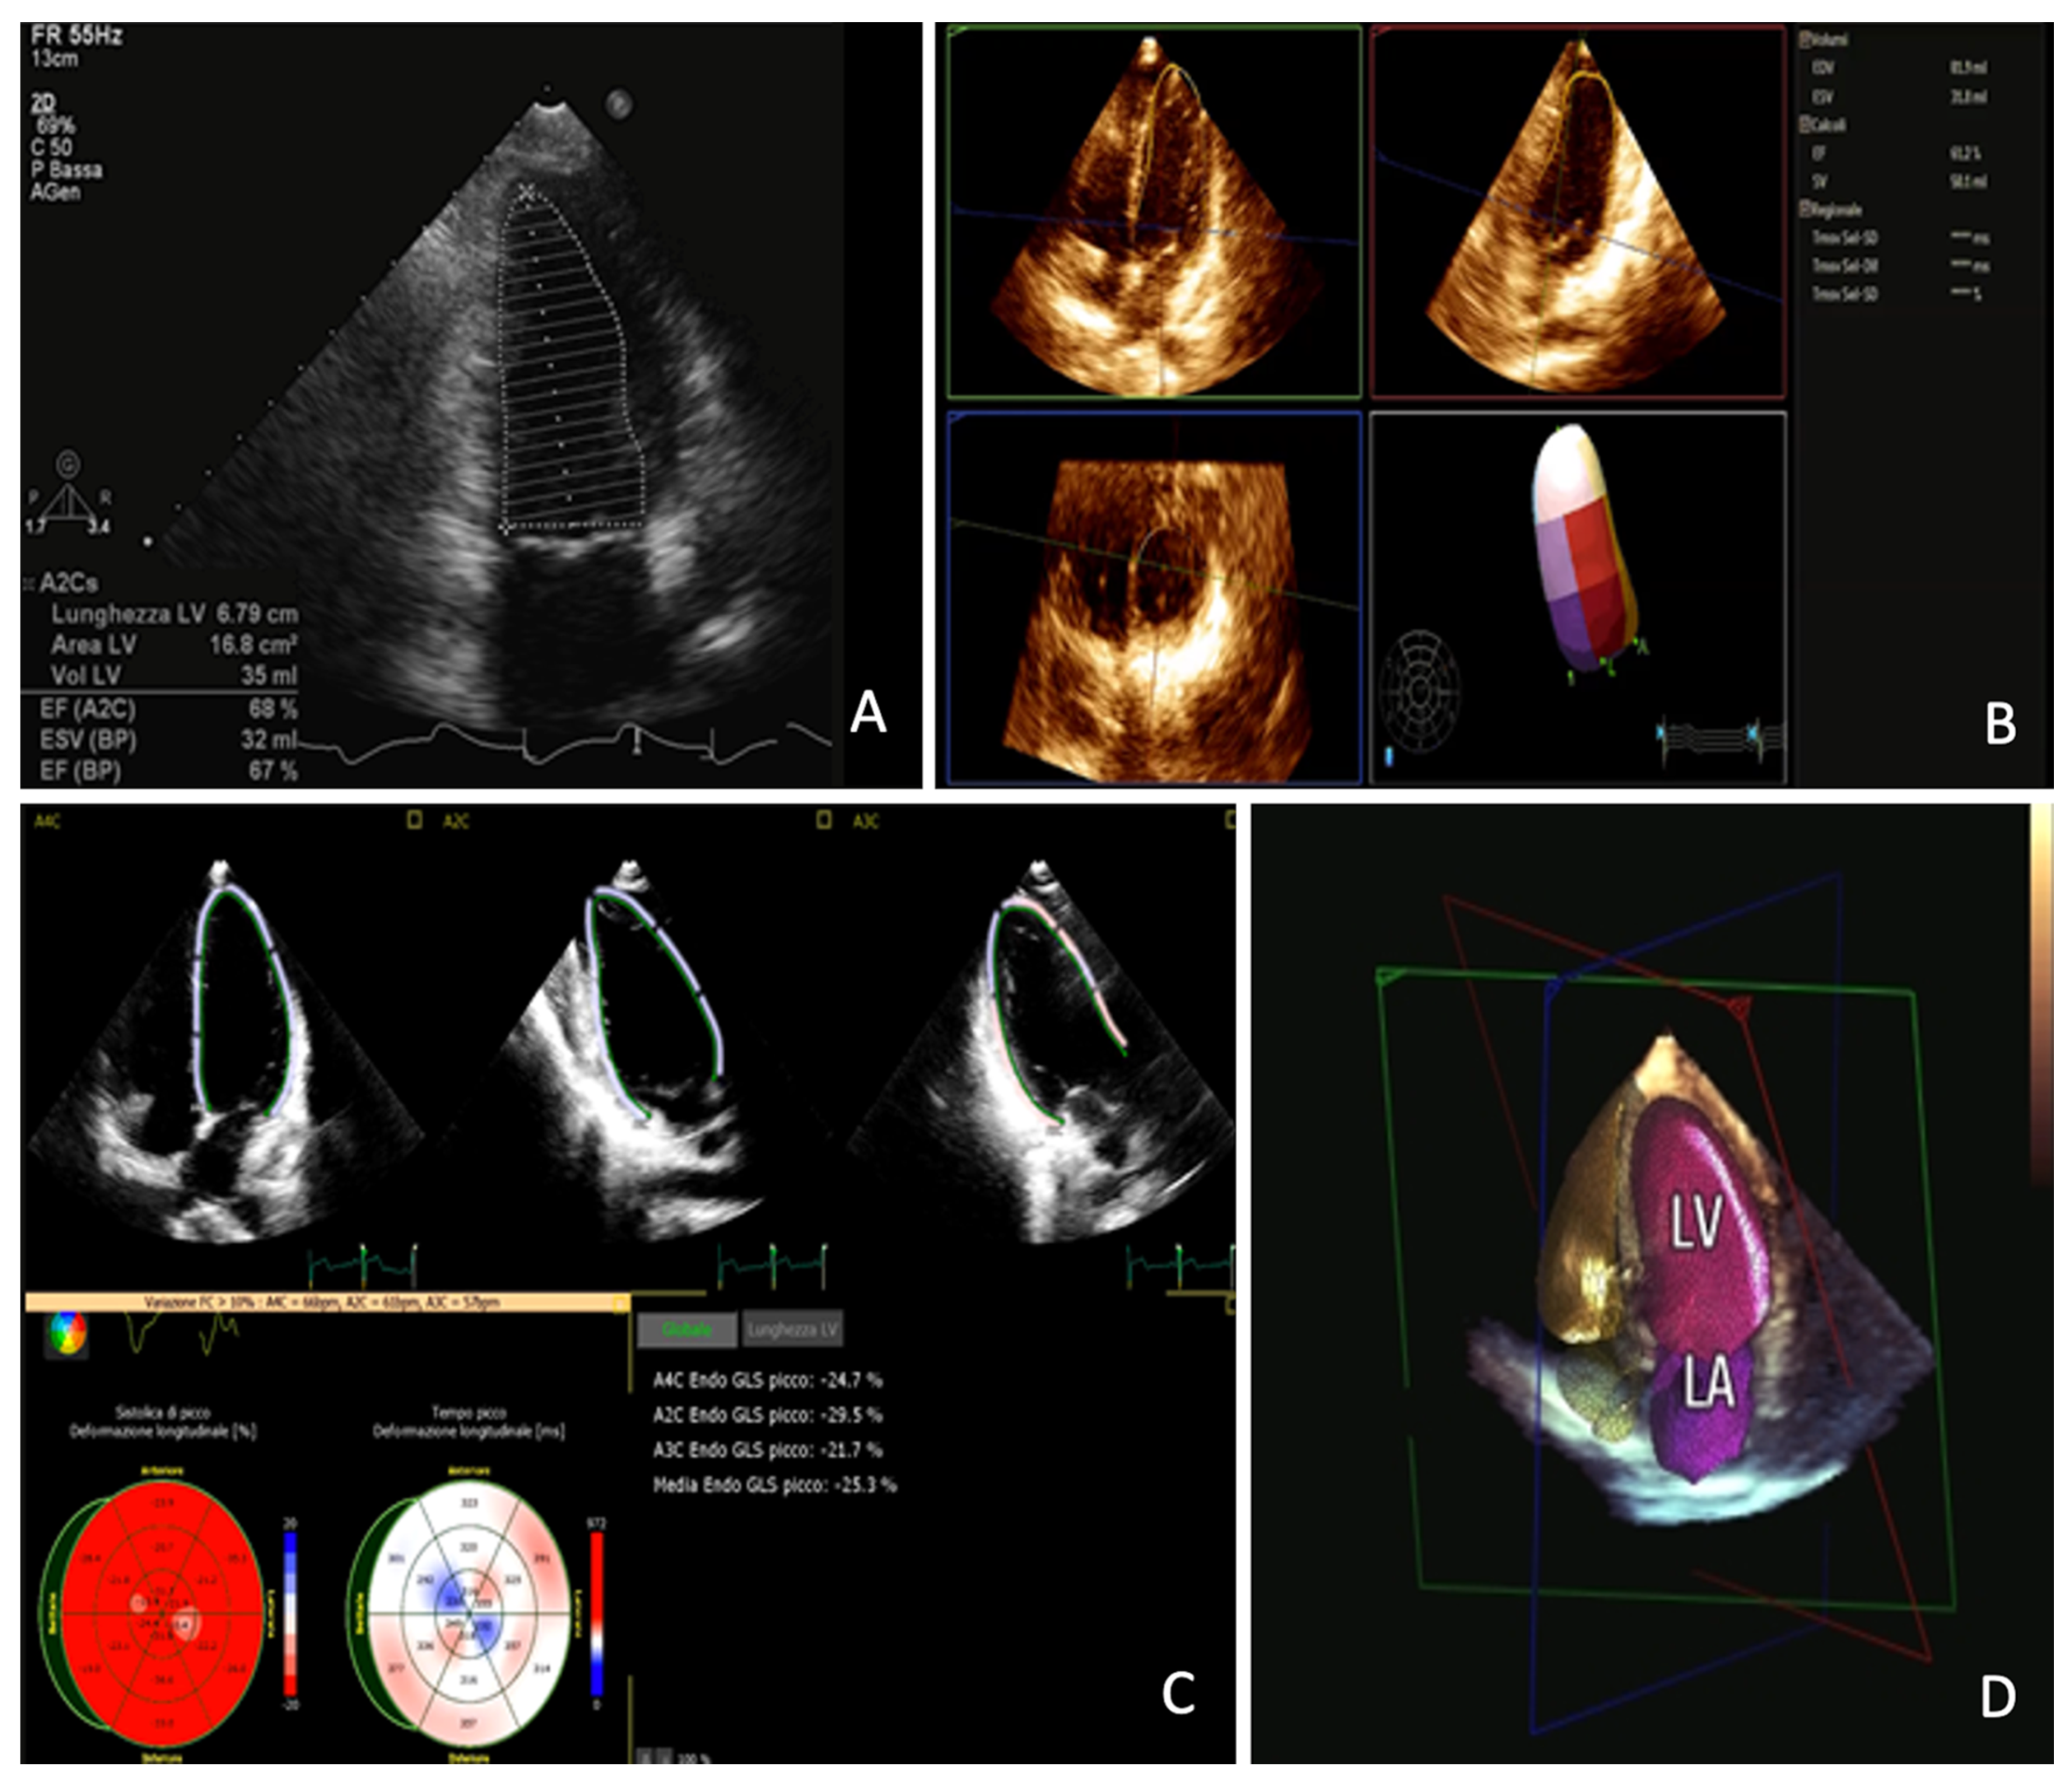

4.1. Assessment of LV Function at Rest

4.2. Role of Strain in Ischemic Cardiomyopathy

4.3. Stress Echocardiography